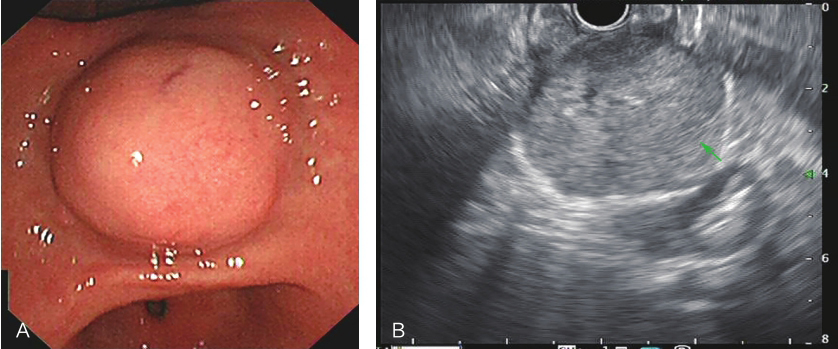

超声胃镜:胃体小弯近胃窦见一半球状隆起,超声下病变处低回声,固有肌层起源,内可见无回声区,边界清楚,腔内外生长,切面大小4.9cm×3.8cm,弹性成像质地偏硬(图4)。腹部B超示:右肾见片状低回声影,边界欠清,直径2.2cm。

图4胃镜提示胃占位病变

A.胃占位位置;B.胃占位层次